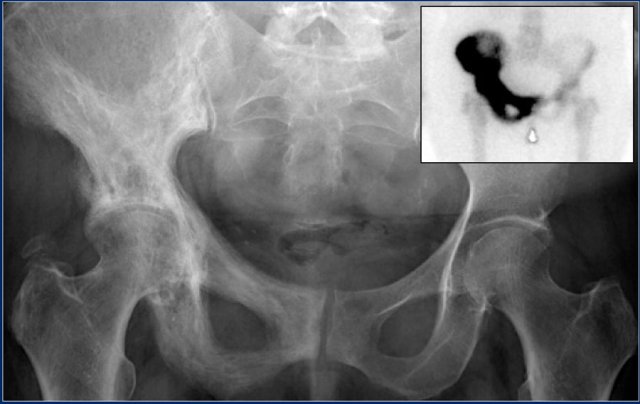

Here a chondrosarcoma of the left iliac bone.

Because of the large dimensions with soft tissue extension on plain radiograph and axial T2-weighted MR image, a high grade chondrosarcoma was suspected.

Biopsy showed grade 2 chondroarcoma.

Continue with the bone scan.

Intense uptake on bone scintigraphy as we would expect in high grade chondrosarcoma.